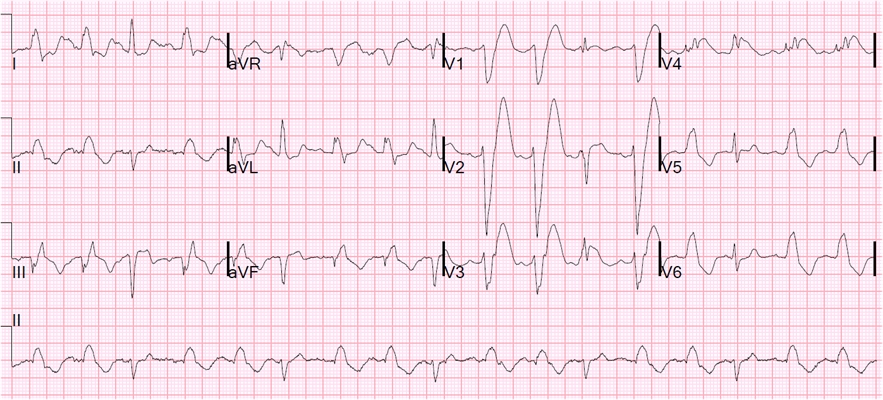

A:預激綜合徵典型的心電圖表現是竇性心搏的PR間期縮短,短於0.12s,而且導聯的QRS波群時間超過0.12s。QRS波群起始部分會有粗鈍,終末部分正常,甚至會導致ST-T波型呈現繼發性的改變,甚至於QRS波群主波方向相反。預激綜合徵是指心房……

A:預激綜合徵是很少見的心律失常,是房室傳導異常的一種類型,提早興奮心室的一部分或全部,引起心室肌提前激動,常合併室上性心動過速。心電圖可見PR間期縮短小於0.12秒;QRS時限延長0.11秒以上;QRS波群起始部粗鈍,繼發性ST-T改變。沒有……

A:預激綜合徵合併房速的時候,心電圖可以出現快速而且寬大畸形的QRS波群,有點類似於室性心動過速,典型的預激波有可能會被覆蓋。合併房速的時候會有極快速的心室率、QRS波群會寬大畸形,也有可能比較易變和複雜。患有預激綜合症合併房速,如果有明顯的心……